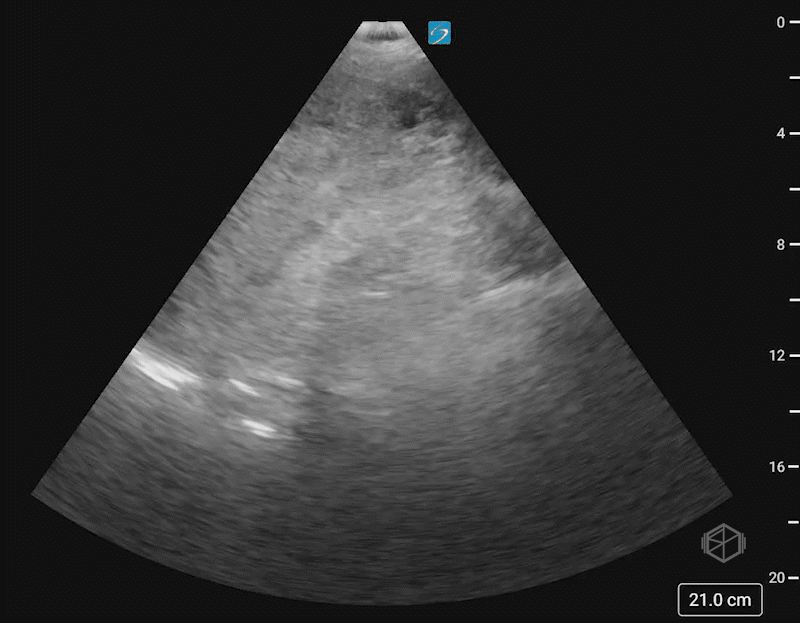

This was the patient’s FAST examination:

This FAST examination is clearly positive, with large amounts of complex fluid near the liver tip in the first clip. In the 2nd and 3rd clip, note the absence of the normal contour of the spleen. There is also free fluid at the tip of the spleen.

The patient had a CT that demonstrated AAST spleen grade grade 5 splenic injury based on active bleeding with hemoperitoneum and splenic laceration and left fourth through eighth rib fractures.

Diagnosis: Grade 5 splenic laceration with hemoperitoneum and active extravasation

• Swirling internal echoes in this scan likely indicate active hemorrhage.